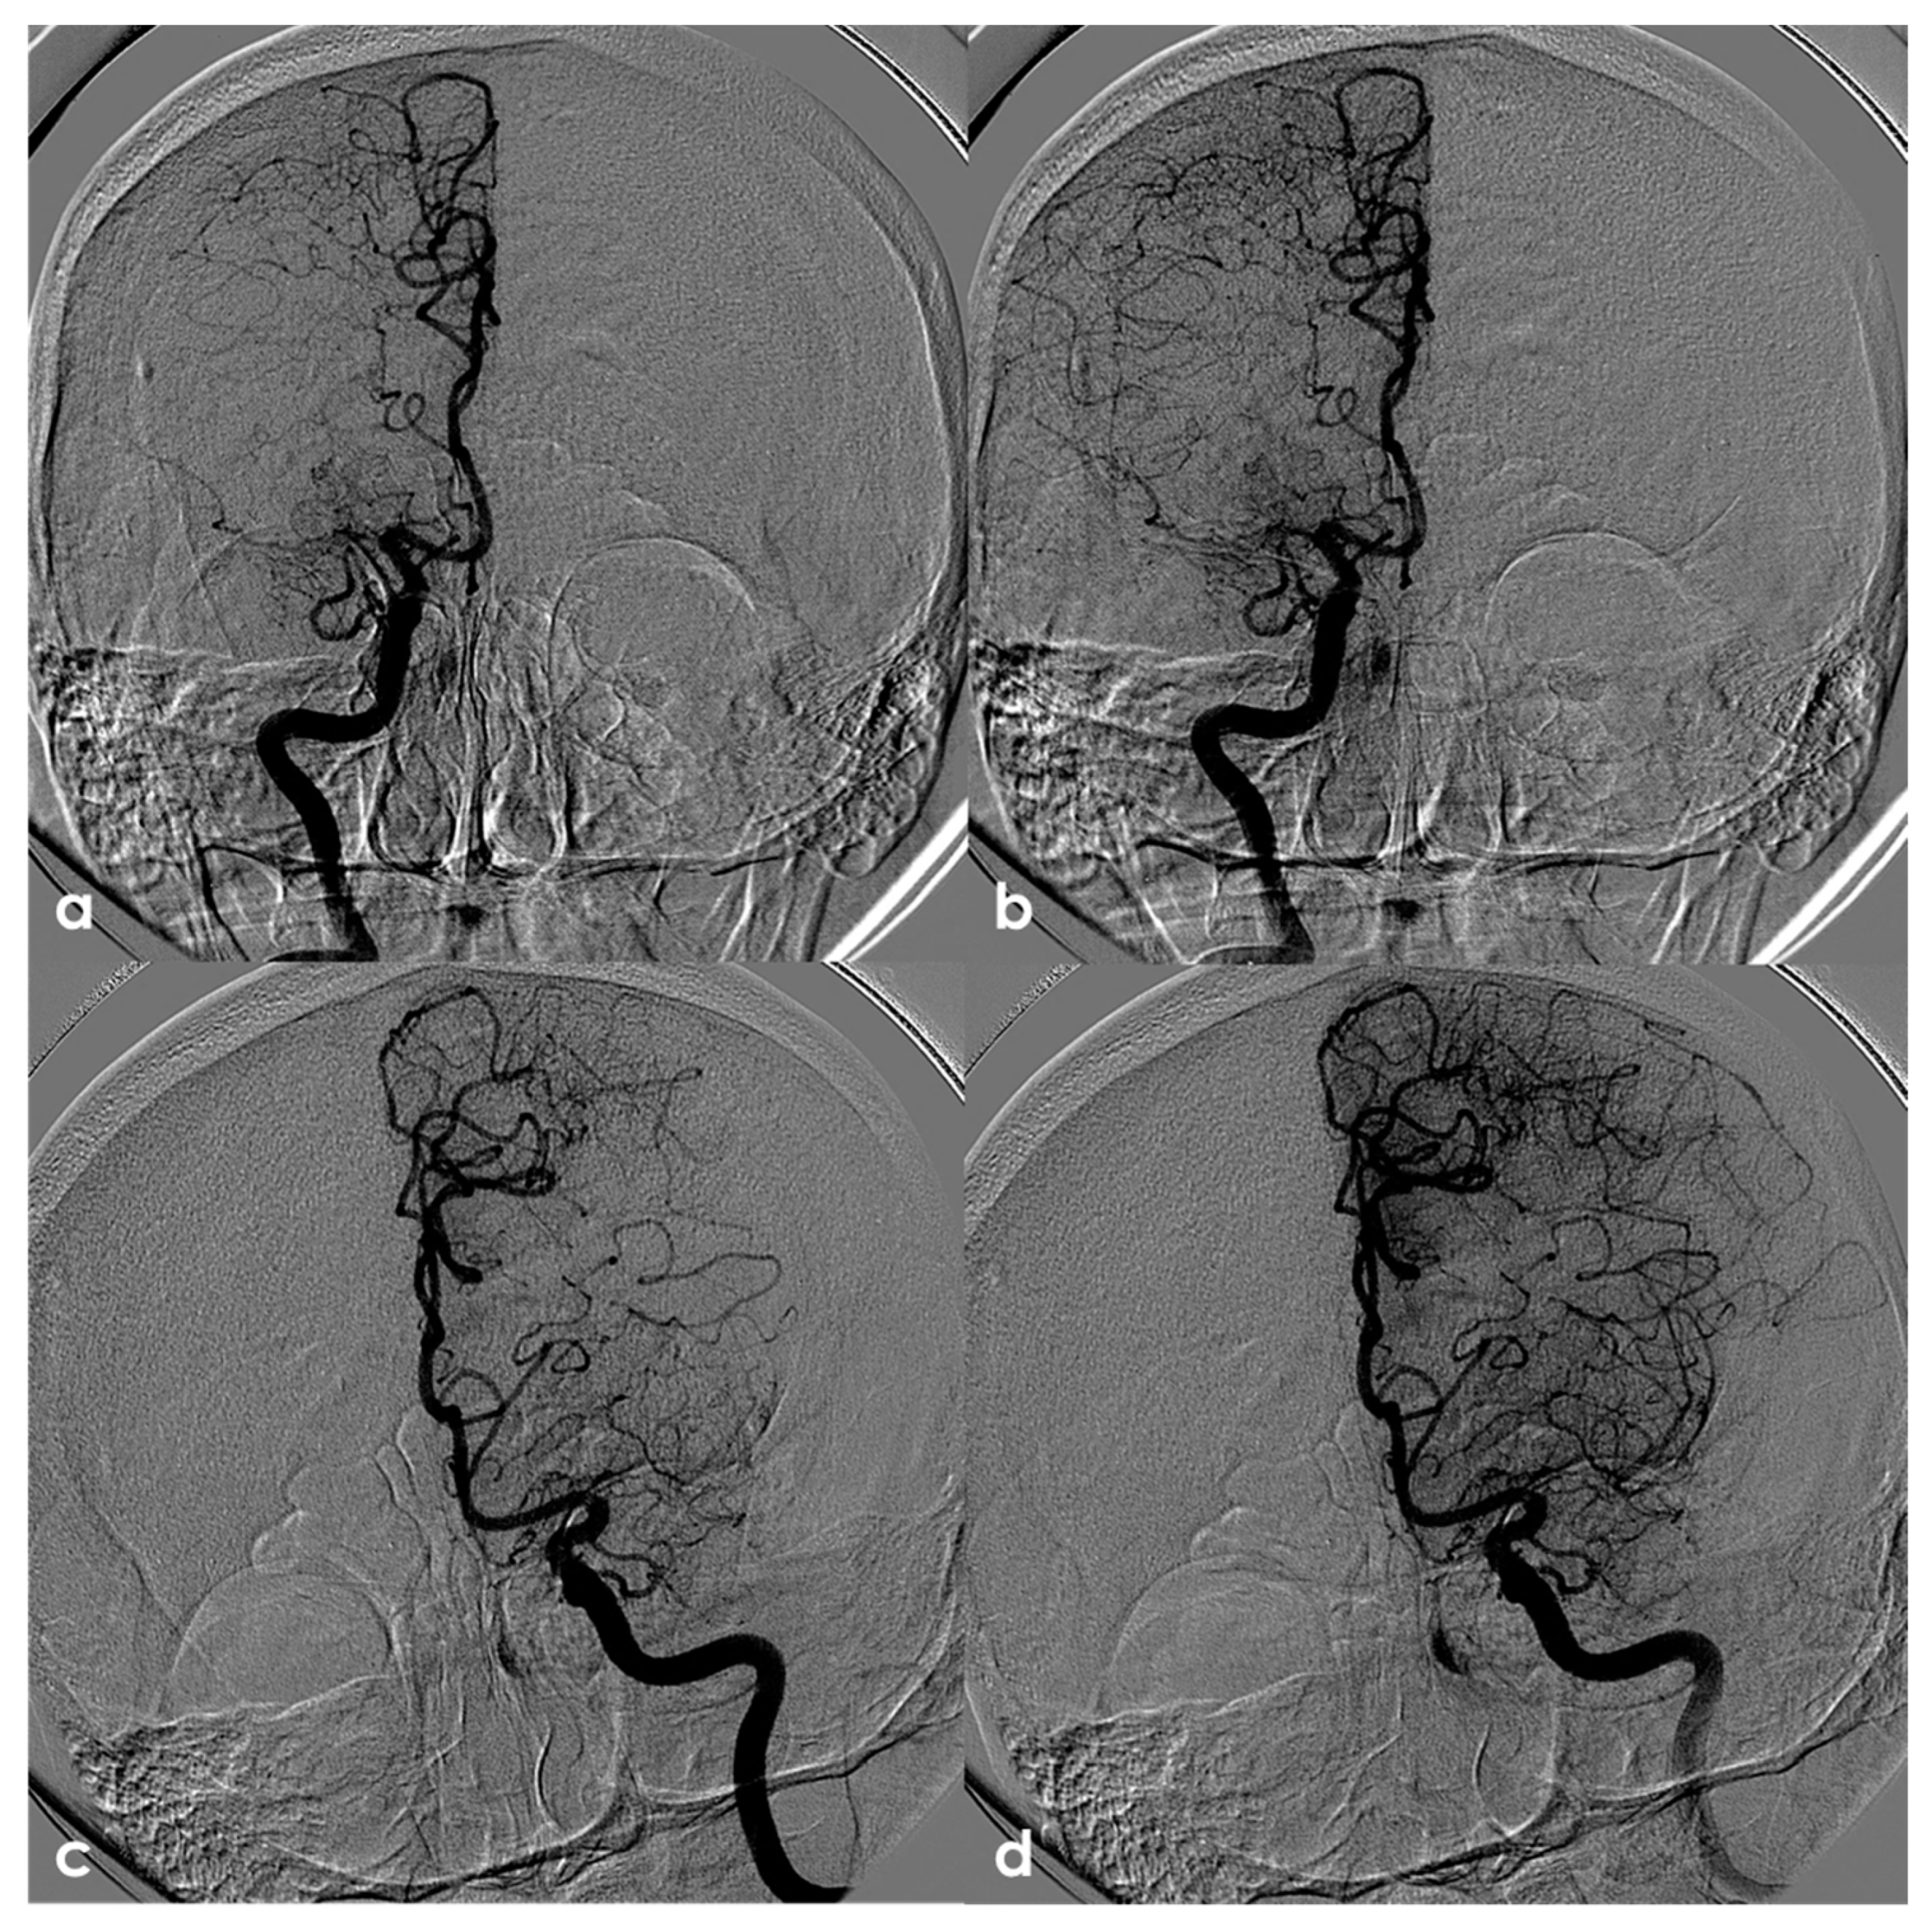

4.2.2. Large-Vessel Involvement